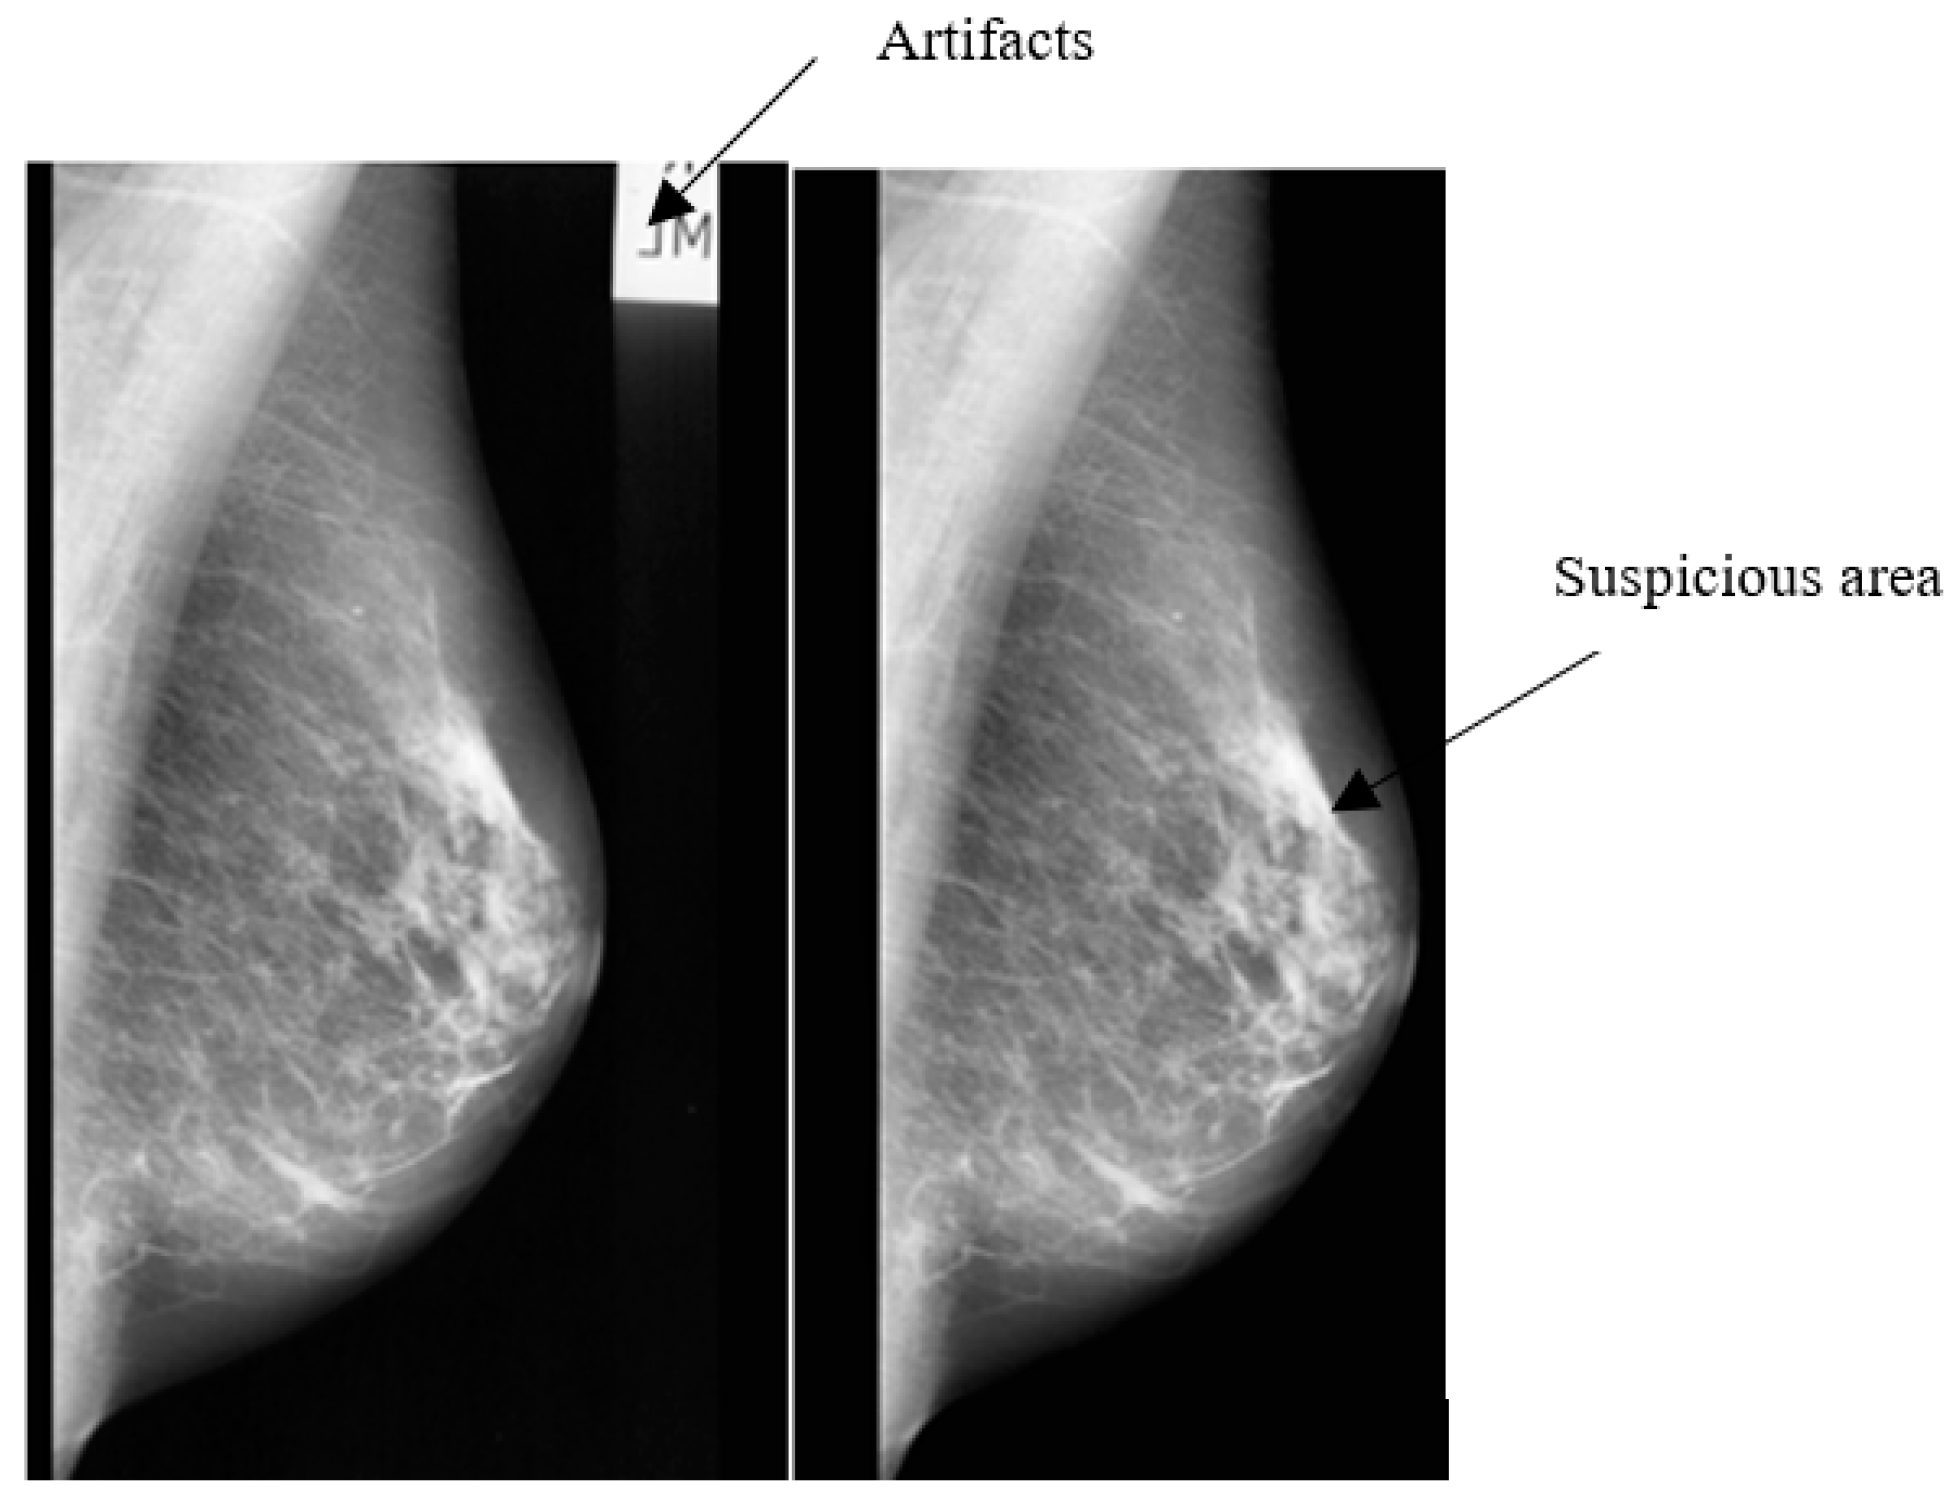

- Eliminate the mammogram image from any radiopaque artifacts, such as labels. This is performed by using thresholding and morphological operations [5]. A global threshold with a value of 18 was found to be the most suitable threshold for transforming the grayscale images into binary (0,1) format [5]. Figure 3 shows the mammogram image with artifacts suppression.